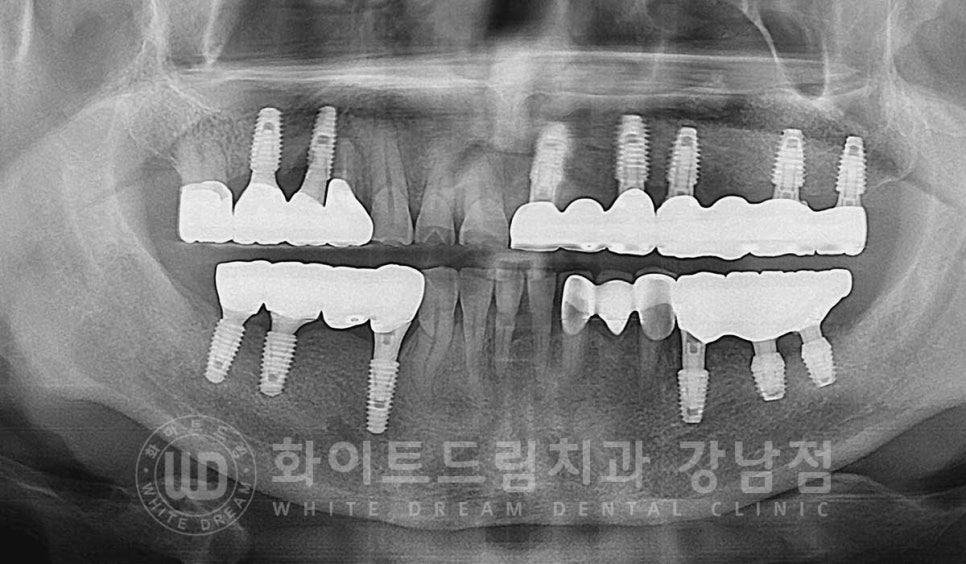

환자분은 최대한 빠르게 임플란트를 성공적으로 치료하고 싶으셔서

임시틀니는 거의 사용하지 않고 생활하셨다고 하며

23.01.30, 5개월 만에 최종 보철을 체결하고 교합 체크 과정을 받으면서

치료를 마무리했답니다.

치료 기간 : 23.08.19 - 24.02.29